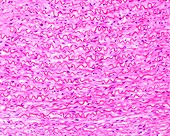

13613516 - Vein adventitia, light micrograph